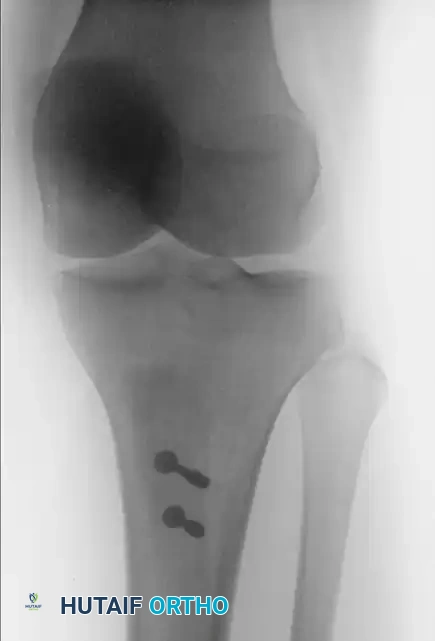

Once optimal tracking is confirmed, temporarily secure the tubercle with two smooth Kirschner wires.

- Fix the osteotomy using two 4.5-mm cortical screws or fully threaded cancellous screws with washers, placed in a lag fashion from anterior to posterior.

- Ensure the screws engage the posterior tibial cortex for maximum pull-out strength.

FIGURE 47-18B: Postoperative lateral radiograph demonstrating anteriorization of the tibial tubercle and secure bicortical screw fixation.

FIGURE 47-18C: Postoperative anteroposterior radiograph showing the medialized position of the tubercle and hardware placement.